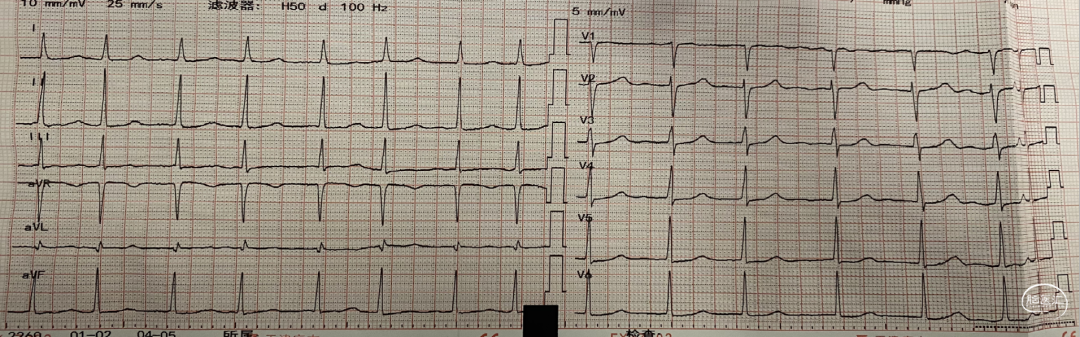

术前心电图提示:心房颤动